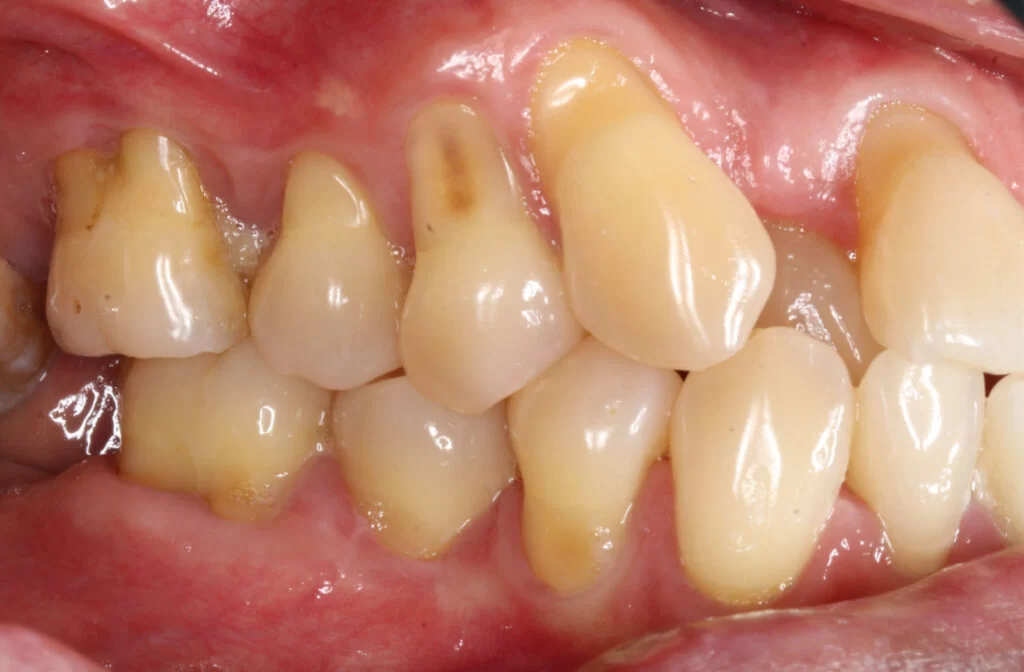

What Causes Gums to Recede and How to Prevent It: Essential Tips for Healthy GumsLearn what causes gums to recede and discover practical ways to prevent gum recession. Find out how to protect your gums from damage and keep your smile healthy.